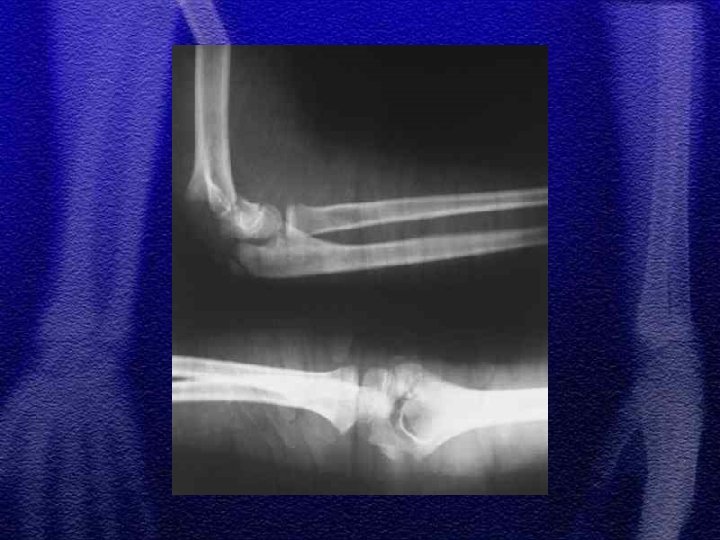

§ Najczęściej występuje typ wyprostny 85% § Wśród złamań typu Monteggia notuje się największą ilość błędów diagnostycznych § Leczenie - próba nastawienia zachowawczego, leczenie operacyjne przy niepowodzeniu repozycji zachowawczej § Należy pamiętać o możliwości wtórnego przemieszczenia odłamów